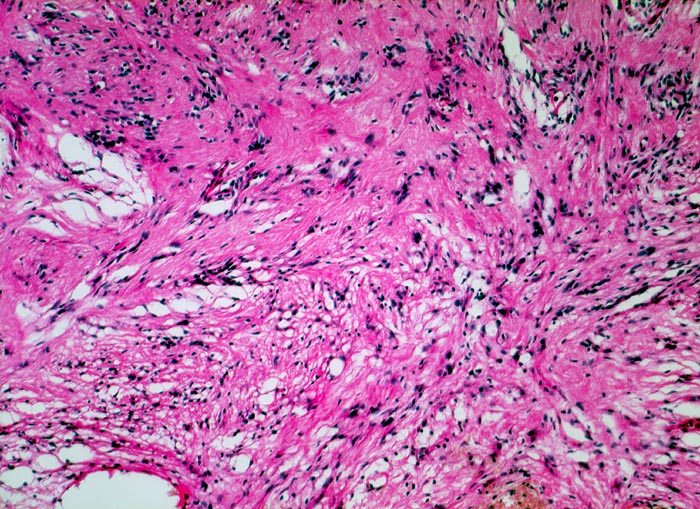

Die histomorphologischen Befunde sind sehr variabel. Am häufigsten bestehen die Tumoren aus Zellzügen mit bipolar orientierten länglichen oder gewellten Kernen und langen Zellfortsätzen. In den sogenannten Antoni A Arealen (> 4295) sind die Zellen in kompakten Bündeln angeordnet, teilweise in Form von Verocay bodies (> 493) (alternierende Anordnung von Kernreihen und Zellfortsätzen). In den Antoni B (> 4296) Arealen bilden die Fortsätze der eher sternförmigen Tumorzellen ein lockeres Geflecht. Einzelne grosse, unregelmässig geformte und hyperchromatische Kerne und flächenhafte Nekrosen, Hyalinisierung oder fokale Verkalkungen sind Ausdruck degenerativer Veränderungen (sogenanntes ancient schwannoma (> 4299)) und dürfen nicht als Zeichen der Malignität fehlinterpretiert werden.

• Antoni B Muster: Lockerer Tumorzellverband mit runden Kernen und spinnwebenartigen Zellfortsätzen.